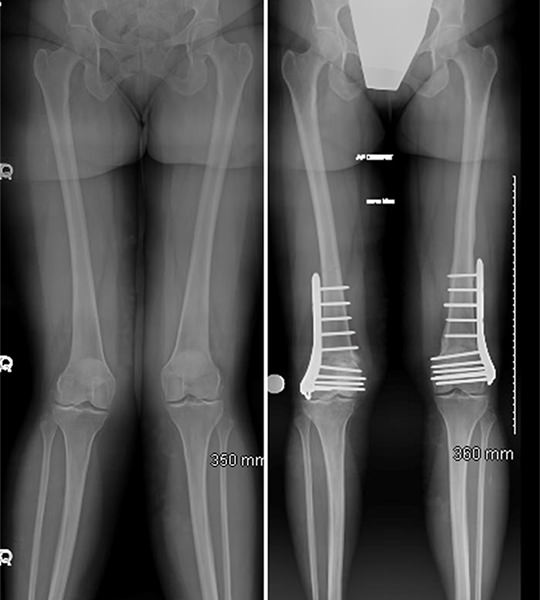

Bone and joint deformities can significantly impact mobility, posture, and overall quality of life. Whether caused by birth defects, injury, or improper healing of fractures, deformities require specialized surgical correction to restore natural alignment and improve function. At our center, we use advanced orthopedic techniques to ensure safe, effective, and lasting outcomes.